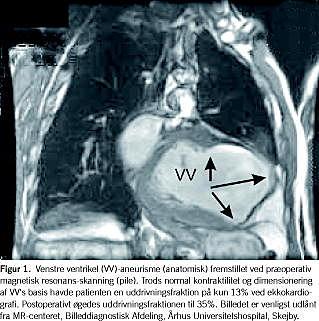

I perioden januar 2002 til oktober 2007 fik 26 patienter foretaget venstre ventrikelaneurismektomi (Tabel 1). Ti af patienterne havde haft tilfælde med ventrikulær takykardi eller ventrikelflimren. Alle patienter havde ægte aneurismer (Figur 1), heraf i et enkelt tilfælde med indhold af en salmonellainficeret parietaltrombe. På trods af at alle patienter kunne anses for at være optimerede i deres medicinske hjerteinsufficiensbehandling (se Tabel 1), var ingen af dem i New York Heart Association (NYHA)-klasse I før operationen. Fem patienter var i NYHA-klasse II, 15 i klasse III og seks i klasse IV. Beregnet ud fra Logistic Euroscore kunne den perioperative mortalitetsrisiko beregnes til 11,9% (1,2-45,6%) [6]. To af operationerne var subakutte. Fem patienter havde implantable cardioverter defibrillator (ICD)-pacemaker præoperativt.

I vores materiale lagde vi ved vurderingen af operabilitet stor vægt på, at patienterne havde tydelige følger efter forvægsinfarkt med et velafgrænset apikalt aneurisme eller akinesi. Derudover er kriterierne for henvisning til eventuel ventrikelresektion, at patienterne har en EF < 35% og er i NYHA- klasse III/IV. For de patienter, vi opererede i NYHA-klasse II, var hovedindikationen angina pectoris. Ventrikelresektion blev således udført samtidig med en nødvendig CABG. Ligeledes var hovedindikationen for de to patienter med en EF> 35% angina pectoris og en enkelt med inficeret aneurismetrombe. For at muligøre rekonstruktion af hjertet fandt vi det også afgørende, at der var velbevaret kontraktilitet i ventriklens basale segmenter uden væsentlig dilatation af venstre ventrikels basis (jf. Figur 1). Til karakteristik heraf benyttedes generelt ekkokardiografi, som i visse tilfælde med fordel kunne suppleres med cinemagnetisk resonansskanning. Forudsætningen for overvejelse af operativ behandling er også, at medicinsk hjerteinsufficiensbehandling er udnyttet fuldt uden tilstrækkelig symptombedring. Formålet med operationen er bedring af ventrikelstørrelse, EF og symptomer, mens fuld medicinsk hjerteinsufficiensbehandling også gives postoperativt. En nedsættelse af medicinforbruget forekommer ikke umiddelbart tilrådelig og kan formentlig på ny medføre manifest klinisk hjerteinsufficiens.